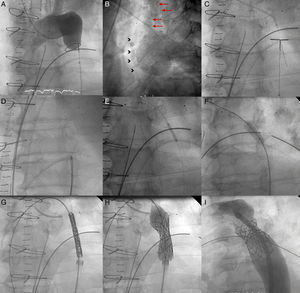

Patient 1, a 57-year-old man in NYHA class III with severe aortic regurgitation and dyspnea, required percutaneous coronary intervention before surgery. Numerous collateral vessels had complete obstruction of the aorta and a giant intercostal aneurysm below the coarctation point (Fig. 1). The aortic obstruction was treated using the technique described and a CS was implanted to exclude the aneurysm. The final outcome was very good; the gradient disappeared and there was a large increase in lumen diameter. We also performed redilation and obtained good apposition of the distal stent edge. The aneurysm could be visualized very faintly following the final injection (Fig. 2). Two days later, the end was tragic when the patient suffered a massive hematemesis and died. Autopsy showed that although the coarctation was well repaired and the stent did not have its cover, leaving the aneurysm in communication with the descending aorta. We believe that the large increase in systolic blood pressure from 70mmHg to 150mmHg after the coarctation point led to a high-pressure retrograde flow into the aneurysm. In the following hours, the aneurysmal bulge ruptured into the esophagus, with fatal gastrointestinal bleeding (Fig. 3).

Figure 2.Coarctation with complete aortic obstruction and giant intercostal aneurysm (patient 1). A, aortography of the arch showing the complete obstruction with the snare in position; B, in the late phases, in 40° left anterior oblique view, large collateral vessel (arrows) that provides circulation into the descending aorta contrasted with a large intercostal aneurysm (arrowheads); C, perforation with Crossit 300 guide wire and insertion into the GooseNeck™ snare; D, guide wire captured with the snare and extraction establishing the radial-femoral line; E, expansion with 2mm×20mm Maverick coronary balloon catheter; F, inversion of the loop, positioning of the 0.035 guide wire, and expansion of the 8mm×20mm Balt balloon catheter; G, positioning the covered stent; H, expansion; I, outcome with good stent apposition to the wall.

Figure 4.Patient 2, ruptured aorta. A, aortography showing a large recoarctation; B, underexpansion of the Palmaz stent. C, post-expansion to 9atm using the Mullins balloon; D, aortic rupture and contrast leaking into the chest (arrow); E, covered stent in the stent prior to expansion; F, expansion of the covered stent in the stent; G, completely sealed aortic rupture.